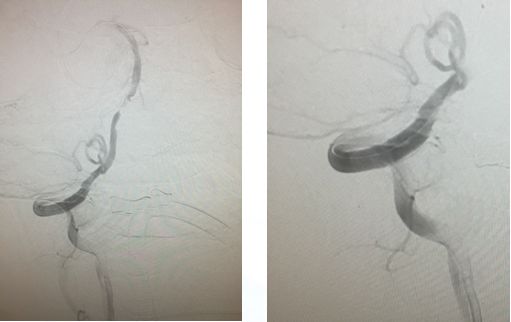

右椎V4段狭窄,2.5*15球囊扩张(应用替罗非班)

13:40:应用3.0*13Apollo支架释放血管再通

自觉头晕、头沉,BP90/60mmHg,嗜睡,精神稍差,言语不清,四肢肌力、肌张力正常,双侧Babinski征(-)。

NIHSS评分2分。

术后复查颅脑CT

出院时查体:言语清晰,四肢肌力、肌张力正常,NIHSS评分0分。